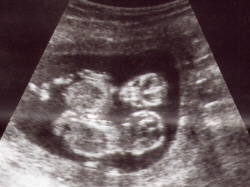

Scanning - Uge 12

CRL= 55 til 74 mm. CRL = 2,2 til 2,9 inch. |  Vægt= 14 g = 0,5 oz. |  |  |  Tvillinger, sonogram scanning. |  Tvillinger i den samme sæk, refereres som 'Monoamniotiske tvillinger'. |

Uge 12 - Fosterudvikling ↑Top↑